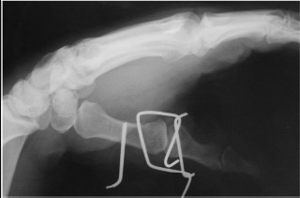

Рис. 3. Внешный вид аппарата

Рис. 4. Рентгенография после 7недель наложения. Полная консолидация перелома

Для непосредственного интраоперационно- го контроля применялся электронно-оптический преобразователь (ЭОП). Стабилизация аппарата в процессе лечения прово-дилась с помощью до-полнительного изгибания спиц. Реабилитация на-чиналась на 2-3 послеоперационные сутки включая активные движения в пястно-фаланговом суставе. В процессе лечения все больные прошли курс восстановительной терапии: ЛФК, физиолечение. Для контроля процессами консолидации через 6-8 недель произведена контрольная рентгенография в двух проекциях. Удаление конструкции было выполнено после рентгенологического подтверждения консолидации (рис. 4).